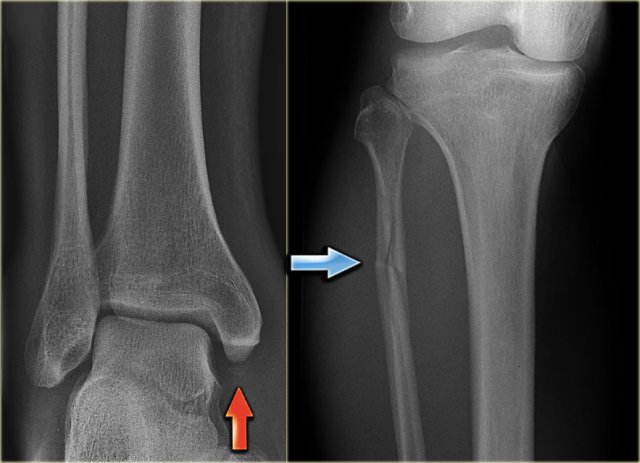

The images show an obvious Weber B fracture.

On the AP-view the linear lucency is the clue to a tertius fracture (red arrow).

It results from subtle malalignment of the fracture fragment.

Likewise in some cases malalignment can result in a linear density.

Continue with the images of the lower leg.

A subtle high fibula fracture is seen (arrow).

Final diagnosis is a Weber C fracture or according to Lauge Hansen: Pronation Exorotation injury stage 4.